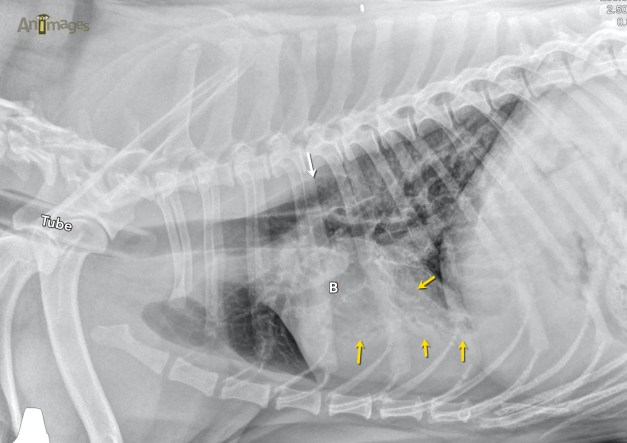

En examinant les radiographies, on constate d’abord la présence d’un tube endotrachéal qui signale une anesthésie générale. L’oesophage (flèche blanche) est modérément dilaté. Les bronches (B) sont dilatées, surtout ventralement, et associées à un pathologie alvéolaire hétérogène en portion ventrale du lobe crânial gauche(flèches jaunes). Ce lobe parait aussi moins volumineux sur la ventrodorsale alors que la silhouette cardiaque est déviée de ce côté. Toutefois, l’obliquité de la projection entraîne un décalage du sternum et de la colonne vertébrale thoracique (pointillés), ce qui pourrait expliquer, du moins partiellement, ce « shift médiastinal« . Ces signes radiographies auraient pu corréler avec un bronchopneumonie par aspiration secondaire à des vomissements ou régurgitations (pouvant avoir été induites par une dysfonction de la motilité oesophagienne).

Comme une anesthésie générale et un décubitus latéral prolongé peuvent affecter la ventilation pulmonaire, le mieux était de répéter les radiographies une fois le chien bien réveillé. C’est ce que le vétérinaire a fait, pour constater que la perte de volume et l’opacification du lobe crânial gauche avaient complètement disparu !

La morale de cette histoire ? Une évaluation optimale des poumons demande que ceux-ci soient bien ventilés au moment de prendre les radiographies. L’anesthésie générale peut rapidement provoquer une atélectasie pouvant faire apparaître des lésions qui n’en sont pas, ou en masquer des réelles (ex. recherche de métastases). Un décubitus latéral de quelques minutes sous anesthésie générale peut avoir un impact diagnostic majeur en provoquant comme dans le cas présent de larges plages de patron alvéolaire. Une anesthésie entraîne aussi fréquemment une dilatation de l’oesophage qui peut être confondue pour un méga-esophage. En ce qui concerne les bronches dilatées de ce patient, un suivi radiographique en latéral sera nécessaire pour confirmer ou infirmer une bronchiectasie chez ce chien. Finalement, le positionnement radiographique peut exagérer un shift médiastinal, comme lorsque le thorax est rotationné lors de la prise des clichés.